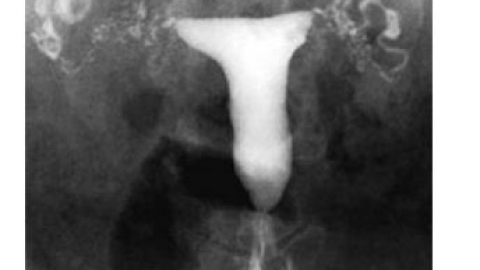

子宫输卵管造影的图像解读

对于1份输卵管造影图像,如何解读图像,挖掘图像背后...